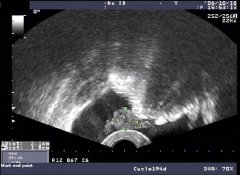

问:妇科专家我在网上看到 盆腔积液15mm ,是指的什么呢?请你告诉我一下! 答: 盆腔积液15mm图片 上面是盆腔积液15mmX光图片:是指事实上盆腔积液分为生理性和病理性,生理性的盆腔积液[详情]